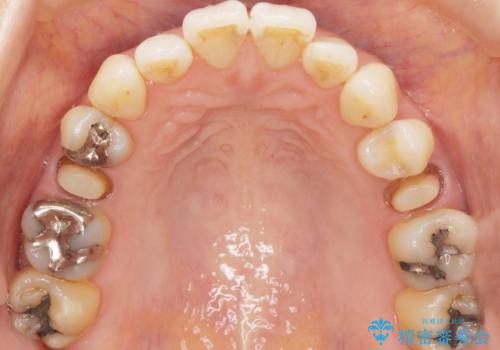

- 歯が欠けてしまったことを主訴に来院された患者様です。

欠けている奥歯(左上5)は失活歯で、保険内の銀の詰め物(メタルアンレー)で治療されていました。

金属の詰め物と土台を除去し、ファイバーコア(金属を使わない強くてしなやかな土台)を植立したのちセラミッククラウンによる補綴治療を行いました。

精査したところ、右上の奥歯(右上5)に根尖病変を認めたため、こちらは根管治療後にセラミッククラウンによる補綴を行いました。